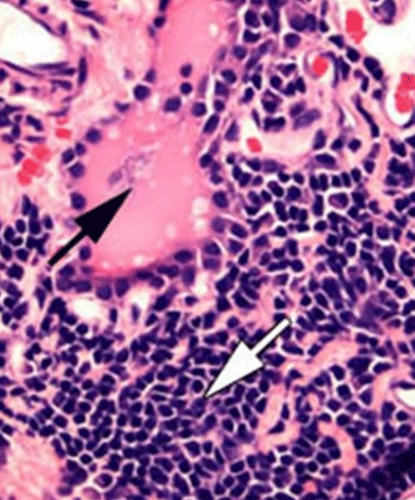

Lymphocytic thyroiditis is the most common form of primary hypothyroidism in canine species. It is believed that it is an autoimmune disease which, through an inflammatory process, leads to the destruction of thyroid follicles and eventually to their replacement with connective tissue (see black arrow).

Histologically, the disease is characterised by diffuse, multifocal infiltration of lymphocytes, plasma cells and macrophages (see white arrow). In parallel, autoantibodies against thyroid antigens such as thyroglobulin, T4 and T3 can be detectable in the blood.